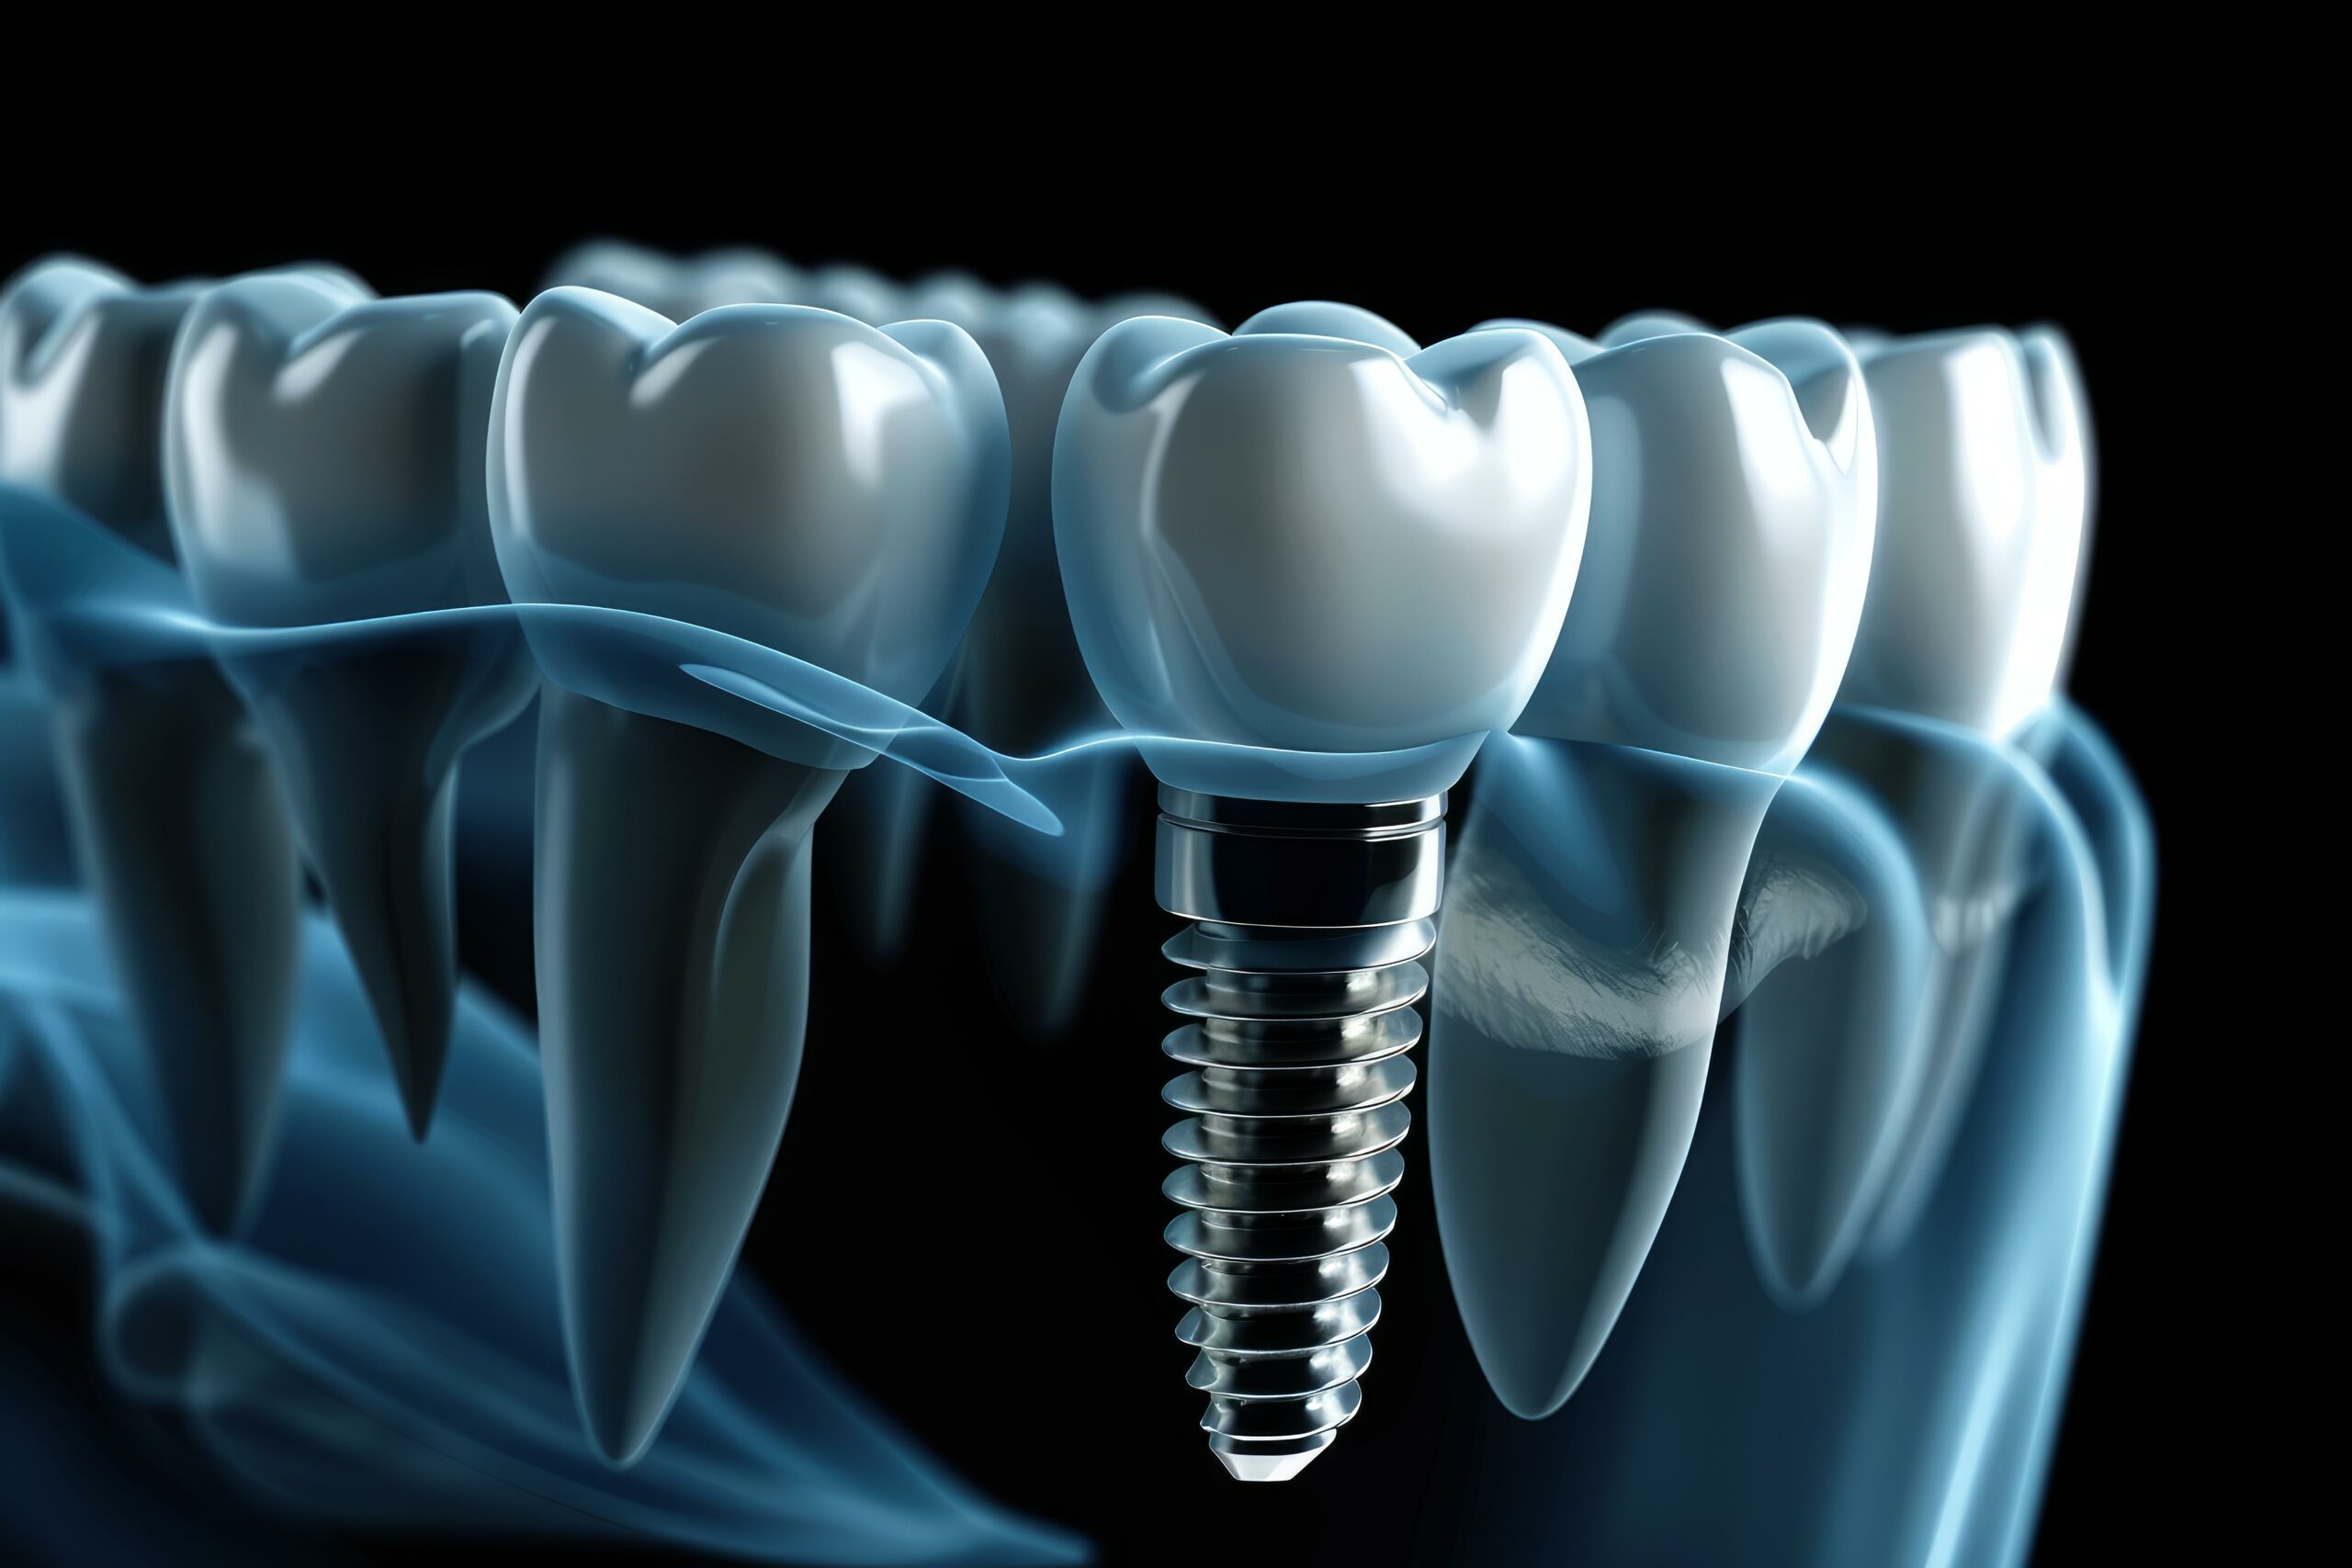

インプラント治療は、歯があった部分の顎の骨に、人工歯根(インプラント体、フフィクスチャー)を埋め込み、その上に人工歯を装着することで、失った歯の機能の改善を図る治療法です。

人工歯根は顎の骨としっかり結合して固定されるため、天然歯に近い噛み心地まで改善できます。